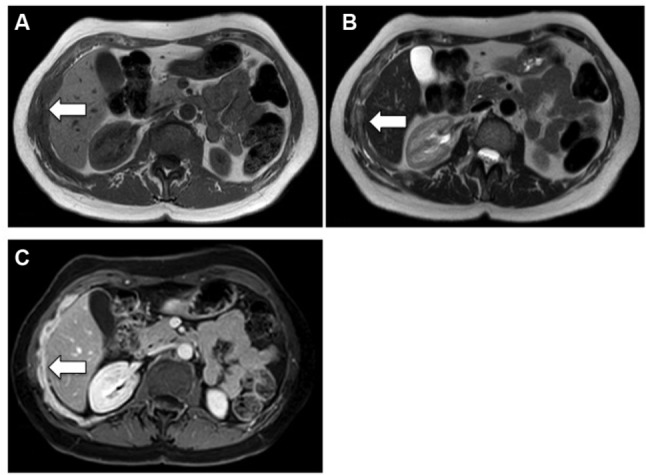

恶性胸膜间皮瘤(MPM)是一种治疗选择有限的疾病,其管理仍然存在争议。通常通过胸腔镜进行诊断,允许多次活检并进行组织学分型,并用于外科候选人的分期目的。国际间皮瘤兴趣小组和国际肺癌研究协会建立的TNM分期系统是临床使用的推荐和最近更新的分类,该系统主要基于手术和病理变量以及横断面成像。对比增强计算机断层扫描是主要的成像程序。目前,最常用的MPM测量系统是改进的实体肿瘤反应评价标准(RECIST)方法,该方法基于垂直于胸壁或纵隔的肿瘤厚度的一维测量。磁共振成像和18f -氟-2-脱氧-d -葡萄糖正电子发射断层扫描的功能成像可以提供额外的分期信息在选择的情况下,尽管这种方法的有用性是有限的患者接受胸膜切除术。MPM的分子重分类和基因表达或miRNA预后模型有可能改善预后和患者选择适当的治疗算法;然而,他们等待在临床实践中引入前瞻性验证。

Malignant pleural mesothelioma (MPM) is a disease with limited therapeutic options, the management of which is still controversial. Diagnosis is usually made by thoracoscopy, which allows multiple biopsies with histological subtyping and is indicated for staging purposes in surgical candidates. The recommended and recently updated classification for clinical use is the TNM staging system established by the International Mesothelioma Interest Group and the International Association for the Study of Lung Cancer, which is based mainly on surgical and pathological variables, as well as on cross-sectional imaging. Contrast-enhanced computed tomography is the primary imaging procedure. Currently, the most used measurement system for MPM is the modified Response Evaluation Criteria in Solid Tumors (RECIST) method, which is based on unidimensional measurements of tumor thickness perpendicular to the chest wall or mediastinum. Magnetic resonance imaging and functional imaging with 18F-fluoro-2-deoxy-D-glucose positron-emission tomography can provide additional staging information in selected cases, although the usefulness of this method is limited in patients undergoing pleurodesis. Molecular reclassification of MPM and gene expression or miRNA prognostic models have the potential to improve prognostication and patient selection for a proper treatment algorithm; however, they await prospective validation to be introduced in clinical practice.